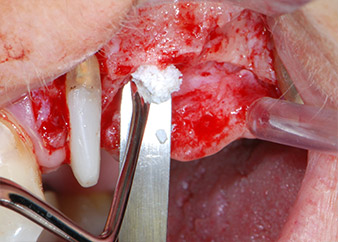

kompletter Verlust von Knochen und Attachment

Abb. 2 und 3: Bei der Freilegung einen Monat nach endodontischer Revision und Beginn einer systematischen Parodontalbehandlung weist die bukkale Wurzel des Zahns 24 einen kompletten Verlust von Knochen und Attachment auf.

Zunächst wurde in einem Versuch, das Paro-Endo-Problem zu lösen, an der verbleibenden Wurzeloberfläche ein vorsichtiges Debridement mit einem piezochirurgischen Gerät vorgenommen (Piezomed, W&H) (Abb. 4); dann wurde der Apex mit dem gleichen Instrument im Sinne einer WSR abgetragen, um das verbleibende infizierte apikale Gewebe zu entfernen (Abb. 5). Eine retrograde Füllung war nicht notwendig, da die orthograde Füllung gerade revidiert worden war.

Brückenpfeiler

Abb. 4: Um den Zahn 24 als vorläufigen Brückenpfeiler zu erhalten, wird das Parodont mit einem piezochirurgischen Sytem gereinigt ...

bukkale Wurzelspitze

Abb. 5 ... und die bukkale Wurzelspitze mit dem gleichen Instrument abgetragen (WSR).